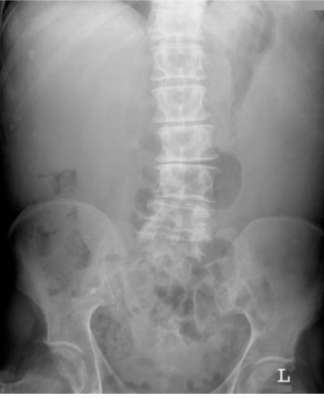

What is this and what type of scan

small bowel obstruction/ileus, abx